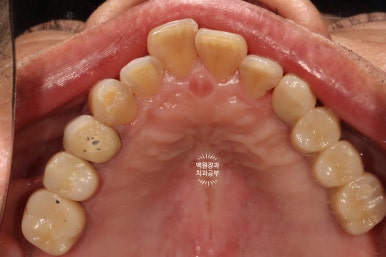

드디어 전체임플란트가 완성되었습니다!!

짜잔!!! 정말 비슷한 색상으로 제작이 잘 되어왔습니다.

최종 크라운을 연결하고나니 그렇게 깔끔할수가 없네요.

위턱 교합면 사진입니다.

오른쪽의 까만색으로 보이는 부위들은 교합조정을 위한 교합종이의 색깔입니다.

충분히 깔끔한 모양새고...

이가 없던 부위는 이가 생겼으니 가장 큰 변화를 이루어냈다고 생각해야겠네요.